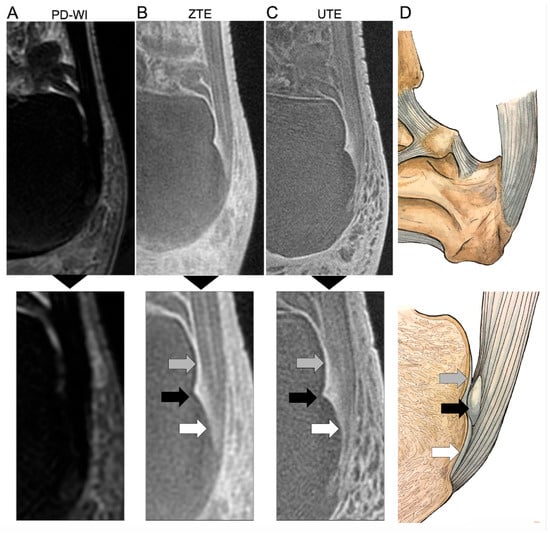

Regarding the PCa, there were no abnormal findings using PD-WI; however, the radiologists described 3/38 (7.9%) as doubtful of pathological findings with the UTE sequence and 5/50 (10%) with ZTE. The rate of false positive findings was not significantly different across the three sequences (p = 0.2818).

Regarding the SCa, there was one abnormal finding using PD-WI; however, the radiologists described 5/38 (13.2%) as doubtful of pathological findings with the UTE sequence and 9/50 (18%) with ZTE. The rate of false positive findings was significantly different across the three sequences (p = 0.0045). In paired post-hoc adjusted analyses, there was no significant difference in the rate of false positive findings with UTE compared to PD-WI, ZTE compared to PD-WI (p = 0.1944 and p = 0.1944, respectively), and between UTE and ZTE (p = 0.9279).

Regarding the ECa, there was 1/50 (2%) abnormal finding using PD-WI; however, the radiologists described 8/38 (23.7%) as doubtful of pathological findings with the UTE sequence and 17/50 (34%) with ZTE. The rate of false positive findings was not significantly different across the three sequences (p = 0.0746).

Regarding follow-up questionnaires, 43/50 (86%) answered them. One volunteer declared the appearance of hindfoot pain about one year after his MRI, which revealed, at that time, abnormal findings on UTE and ZTE sequences (but not on PD-WI) at PCa and SCa locations.

Figure 4 and Figure 5 illustrate the MRI findings described as pathological. Regarding the five patients with abnormal findings on the ECa with both UTE and ZTE, the retrospective reading confirmed the presence of high SIs of the ECA and Achilles tendinous fibers surrounding enthesophytes (Figure 4). Regarding the two volunteers with abnormal findings on the SCa and PCa on both UTE and ZTE sequences (including the volunteer who developed hindfoot pain one year later), the retrospective reading confirmed the presence of focal erosion at the SCa and high SIs of the PCa and its surrounding fibers (Figure 5).

Figure 4. Abnormal findings in an asymptomatic volunteer involving the periost and the sesamoid fibrocartilages reported during the consensus reading. The healthy volunteer was a 29-year-old male. Two consecutive slices are shown for each sequence, i.e., proton density weighted imaging (PD-WI) (A,B), ZTE (C,D), and UTE (E,F). Abnormal findings involving the periost cartilage on UTE and ZTE sequences (but not on PD-WI) corresponded to an ill-defined thick area with high signal intensity (white dashed arrows). Abnormal findings involving the sesamoid cartilage, seen on all sequences, corresponded to a focal bone edema (white continuous arrows). However, the patient did not declare hindfoot pain during follow-up.